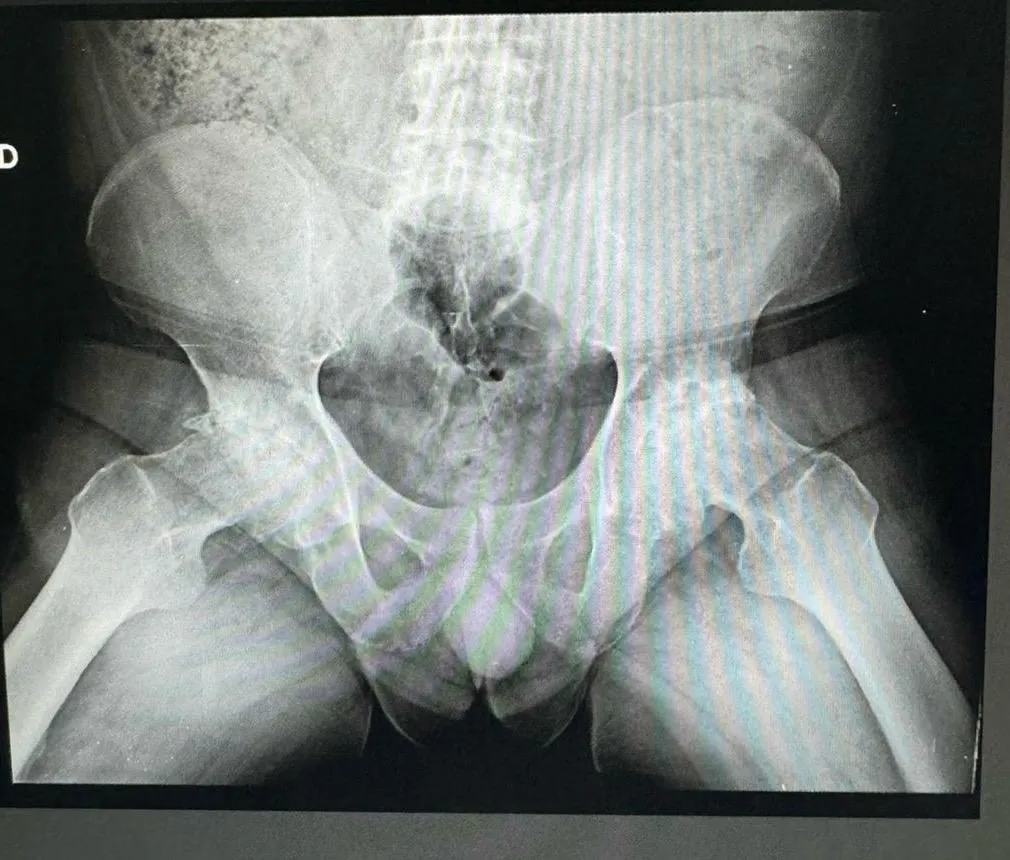

Diagnóstico: Coxartrosis Bilateral Avanzada

Las radiografías preoperatorias revelan el grado de deterioro articular en ambas caderas. Se observa pérdida del espacio articular, deformidad de las cabezas femorales y cambios degenerativos avanzados característicos de una artrosis de larga evolución.

Radiografía preoperatoria de pelvis AP mostrando coxartrosis bilateral avanzada en paciente de 64 años

Radiografía preoperatoria de pelvis AP: coxartrosis bilateral avanzada con pérdida significativa del espacio articular en ambas caderas.

Radiografía preoperatoria de pelvis mostrando deformidad de cabezas femorales por artrosis bilateral

Vista alternativa: deformidad de ambas cabezas femorales con cambios degenerativos avanzados.